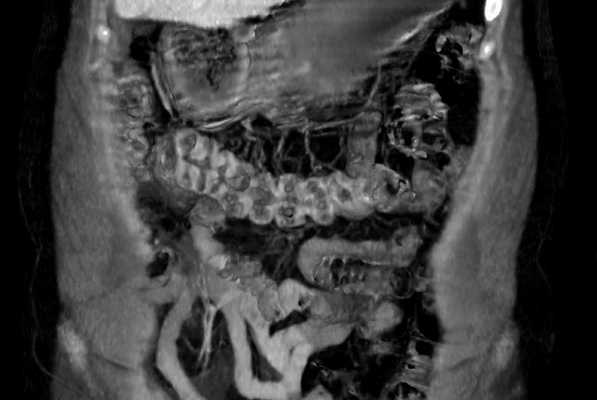

Что такое МРТ кишечника — это бесконтактный метод диагностики средних и конечных отделов пищеварительного тракта. Томография позволяет визуально оценить состояние органа, обнаружить воспалительные, дегенеративные процессы, опухоли. В отличие от эндоскопии, МРТ не создает дискомфорта, болевых ощущений, это полностью неинвазивная методика. Процедура хорошо переносится, может проводиться неоднократно, по потребности.

Магнитно-резонансная томография назначается в качестве основного или дополнительного метода диагностики болезней пищеварительного тракта.

Несмотря на различные мнения, разногласия, ответ на вопрос, можно ли сделать мрт кишечника, положительный. Томография используется для диагностики прямой кишки, тонкого кишечника, толстой кишки. Единственная оговорка — орган представляет собой полую трубку, потому без специальных мер визуализируется плохо. Перед проведением процедуры нужна подготовка. Виден ли на МРТ кишечник, зависит от его содержимого. Потому до начала процедуры проводят очищение ЖКТ, применяют контрастирующие препараты.

При правильной подготовке, визуализация не представляет сложностей. Магнитно-резонансная томография назначается при подозрениях на воспалительные, дегенеративные, онкологические процессы, при наличии симптомов, происхождение которых не до конца понятно. Среди показаний к МРТ кишечника: